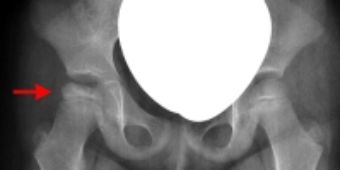

Die Krankheit verläuft in vier Phasen auch „Stadien“ genannt. Die erste Phase (Kondensationsstadium) ist durch eine vermehrte Knochendichte des Hüftkopfes charakterisiert. In der zweiten Phase (Resorptionsstadium) werden die nicht durchbluteten, abgestorbenen Knochenzellen abgebaut, die betroffenen Anteile des Hüftkopfes sehen auf dem Röntgenbild wie aufgelöst aus, der Hüftkopf wird weich und kann sich verformen. In der dritten Phase (Aufbaustadium, Remodellierungsstadium) baut sich der Hüftkopf wieder auf, die Knochenzellen gewinnen an Kalksalzgehalt, der Knochen wird härter und widerstandsfähiger, radiologisch sind zunehmend knochendichte Areale sichtbar. Die vierte und letzte Phase (Residualstadium) ist durch unterschiedlich ausgeprägte Veränderungen der Hüftkopfform gezeichnet. Die Umbauprozesse sind abgeschlossen, der Hüftkopf hat seine endgültige Form angenommen, eine weitere Abrundung ist nicht mehr zu erwarten. Die Krankheit verläuft im Regelfall insgesamt ca. 2-3 Jahre, es sind aber auch längere (protrahierte) Verläufe insbesondere bei älteren Kindern bekannt.

Von den bildgebenden Verfahren ist die Röntgendiagnostik der goldene Standard. In manchen Fällen kann zusätzlich eine MRT-Untersuchung erforderlich sein. Bei deutlicher Einschränkung der Beweglichkeit und Verdacht auf ein s.g. „Hinge Abduction“ Phänomen kann eine dynamische Röntgendurchleuchtung indiziert sein, bei der zur besseren Darstellung Kontrastmittel in das Hüftgelenk injiziert wird. Aus diesem Grund erfolgt die Untersuchung in einer kurzen Narkose.